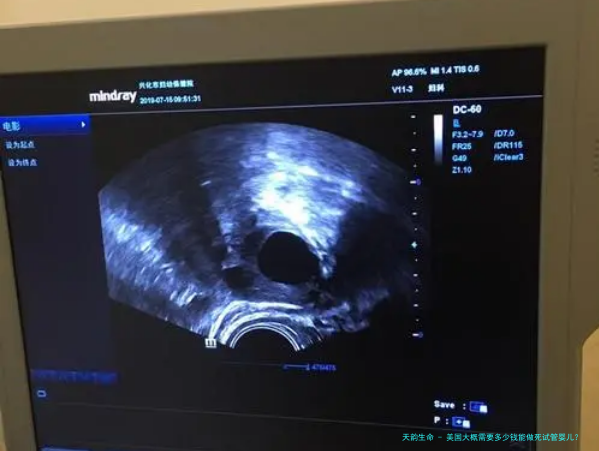

美国大略须要好多钱能做死试管婴儿?试管婴儿辅助生殖技术是一种现助孕育技术,能够帮助那些自然受精困顿的夫妇实现生育梦想。其中死试管婴儿技术是一种多见的辅助生育技术,其费用因地区和医院的不同而不同。本文将以美国为例,推荐死试管婴儿技术的费用和注意事项。

死试管婴儿技术是指将经由特殊处置的死亡或不活跃的子注入子中进行受,然后将受移植到女子宫内进行妊娠。这种技术的费用因地区和医院的不同而不同,一般括下列费用: